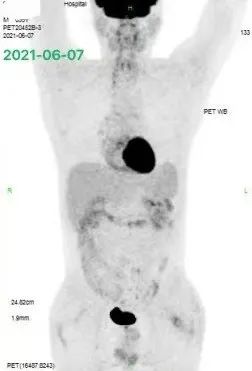

由于患者治疗中出现了进展,在当地参加了 CAR-T 细胞治疗的相关临床试验,在经过一疗程 R-CHOPE 方案桥接治疗及 FC 方案预处理后,患者于 2020 年 3 月接受了一次鼠源 CD19 CAR-T 细胞输注,输注后经历了 2 级 CRS 反应,随后在输注后 1 个月的早期评估 CT 中可见肿瘤明显缩小。

随后患者在 2020 年 4 月接受了 CD22 CAR-T 输注,作为序贯治疗。治疗后患者出现发热,胸闷,咳嗽以及间断的咯血。当地医院考虑 CRS 反应可能,给予相应的处理。CAR-T 细胞扩增情况具体不详。然而,在第二次 CD22 CAR-T 输注后的一个月,患者进行了 PET-CT 的评估,结果提示为肿瘤进展,如下图 3: